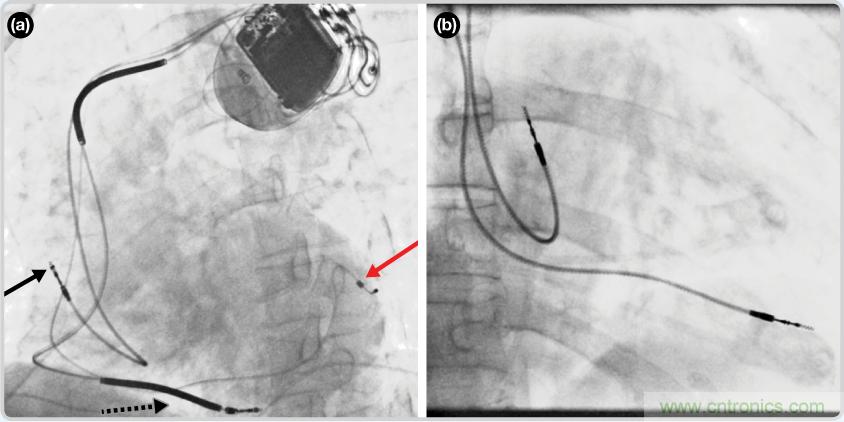

CRT器件在圖4(a)中的透視圖像中可以看見。醫(yī)師就是利用這種影像來放置導(dǎo)聯(lián)線的。對于非專業(yè)人士來說,這種影像是很難解讀的??梢钥吹叫呐K淡淡的輪廓——這是搏動中的心臟的靜態(tài)視圖。起搏器位于右心房上,心臟頂點指向右下方。在這個典型的導(dǎo)聯(lián)線放置實例中,黑色箭頭指向右心房導(dǎo)聯(lián)線。虛線黑色箭頭指向右心室導(dǎo)聯(lián)線。紅色箭頭標(biāo)示的導(dǎo)聯(lián)線只能看到一部分,這是左心室導(dǎo)聯(lián)線(紅箭頭指向電極尖端)。圖4(b)展示的是雙腔起搏器的典型導(dǎo)聯(lián)線放置透視圖像。右心房導(dǎo)聯(lián)線指向上方,置于右心房中。右心室導(dǎo)聯(lián)線則位于右心室頂部。

檢測并區(qū)分心臟起搏偽像

圖4. 起搏器導(dǎo)聯(lián)線放置的透視圖像3 (a). 單腔起搏器;(b).雙腔起搏器